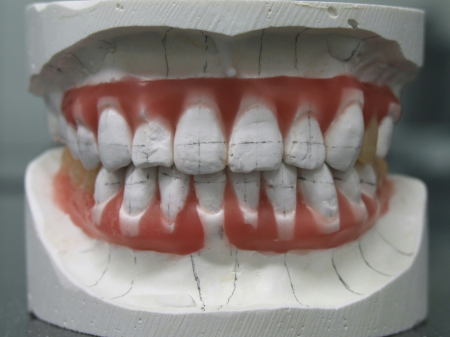

したがって右下前歯を動かさない計画のもと右下前歯の位置を基準としてそれ以外の歯を並べ直して理想的な歯並び、噛み合わせを再現した「セットアップ模型」を製作しました。

セットアップ模型:患者様の歯型をもとに作製した模型の歯の部分を切りだしてバラバラにしてから理想的な位置に並べ直して、咬合治療のゴールをシミュレーションし、確認するために用います。

このセットアップ模型を計測することでインプラントを埋入しなければならない正しい位置を知ることができます。

☆今回は右下前歯の位置を動かさない計画でしたので、治療前の右下前歯の位置を基準にインプラント埋入位置を決定しました。もし下顎の前歯を後方に移動したり、正中を変更したりする計画の場合にはこの移動量を加味してインプラント埋入位置を算定する必要があります。